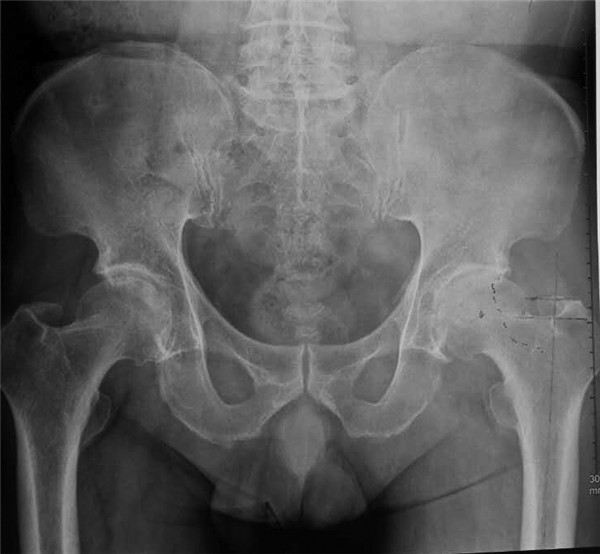

近日,由我院骨科王坤正教授带领王春生副教授、杨佩副教授、张子琦博士等人组成的优秀手术团队,在我院麻醉科手术科的全力配合下,完成了西北地区SuperPATH微创人工全髋关节置换术。手术过程非常顺利,患者术后康复状况良好。

微创全髋关节置换微创化是关节外科医生一直探索的目标。SuperPATH的出现,让我们真正看到了微创全髋关节置换时代的到来。并非切口越小就越微创,微创技术并不单单指切口的大小,切口小仅仅是微创手术的一个特点,而不是微创手术追求的唯一目标,如果片面地为了追求小的手术切口,过多损伤关节周围的肌肉、韧带,手术部位暴露不充分,致使手术假体安装的位置不准确,反而是因小失大,得不偿失,在保证手术部位得到充分显露的基础上,更重要的是保护关节运动所依赖的韧带和肌肉,尽量使切口越短越好。SuperPATH技术手术切口长度6cm--8cm;不需要切断外旋肌,经梨状肌和臀小肌的间隙进入,几乎保存髋关节周围所有的肌肉功能;几乎保留了完整的关节囊;手术操作过程中不需要外科脱位(术中不造成肢体极度的旋转与扭曲); 髋臼侧仅仅要求1cm的皮肤切口就可以完成。

该技术最大限度的维护了植入假体的稳定性,患者返回病房麻醉恢复后就可以下地自主行走,并在术后1月内就允许患者进行髋关节较大范围活动,这对于医患双方无疑是双赢的。